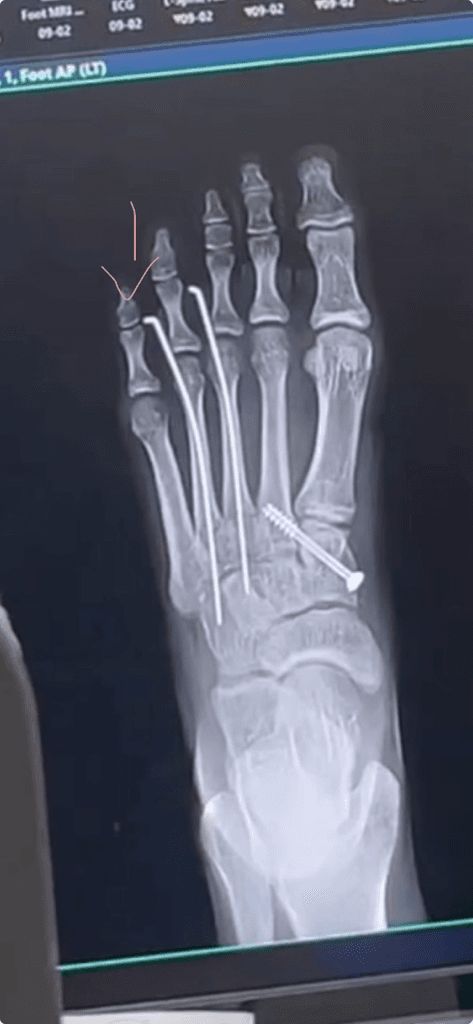

발가락 핀이 휘어요..어떻게 해야 해요..?

이거 지금 다리 상테 인데요 그 원레 핀이 빠같에 있고 똑바로 있는데 어제 함 빼서 봣는데 그 사진이 표시한 그 발가락 핀이 휘는거 예요 근데 그 완전이 휘어서 그 엎 발가락 까지 아파요.. ㅠㅠ 이거 휘면 재 수술 해야 대나요...??? 문제가 잇어요?

체중부하를 하거나, 앞쪽 관절에 의해 압박이 오기 때문에 옆으로 휘는 것은 정상적으로도 볼 수 있습니다.

하지만 새끼 발가락에 상처등이 생기고 통증이 있으시다면 핀의 위치를 일부 조절 받으시는 것이 좋겠습니다.